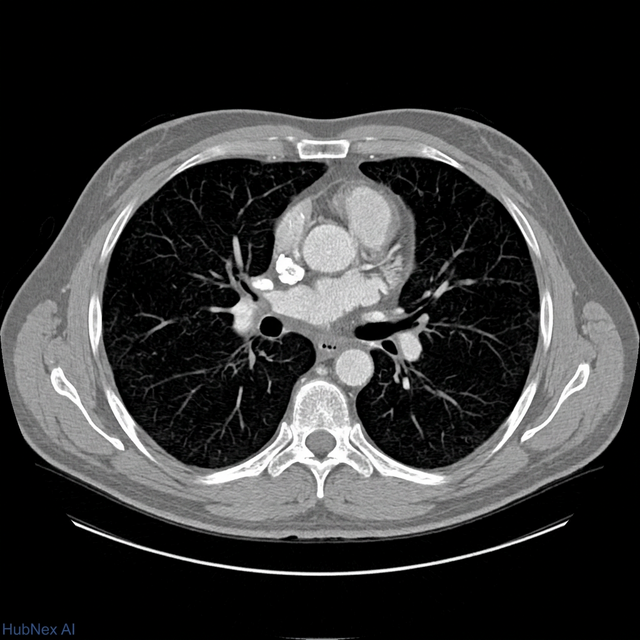

AI annotations, bounding boxes, and measurements are baked directly into the DICOM — rendered as Secondary Captures readable in any viewer. Clinical history and labs are pre-populated into your dictation software.

Open the study in the same viewer you use every day. No retraining. No new hanging protocols to configure. Subspecialty routing means you only see cases matched to your expertise.